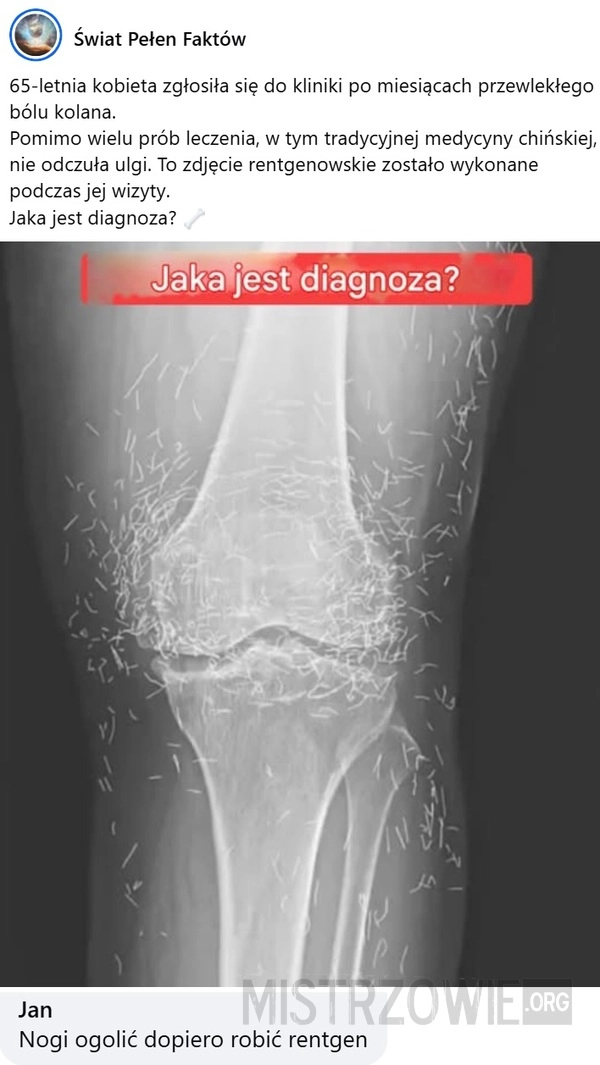

Kolce

Ból